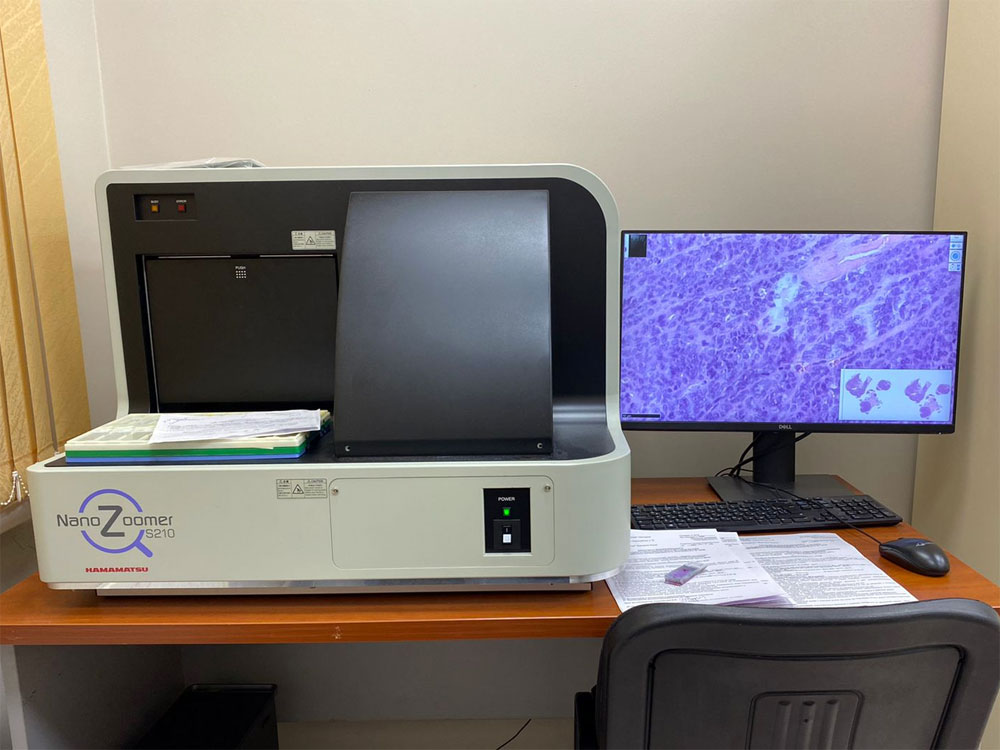

Пироговский Центр продолжает реализовывать план мероприятий в рамках федерального проекта «Борьба с онкологическими заболеваниями»

Благодаря участию Центра в федеральном проекте «Борьба с онкологическими заболеваниями» ряд отделений Центра получили новое оборудование, необходимое для диагностики и лечения пациентов с подозрением или уже выявленным злокачественным новообразованием. В 2022 году запланирована организация Отделения лучевой терапии Центра.